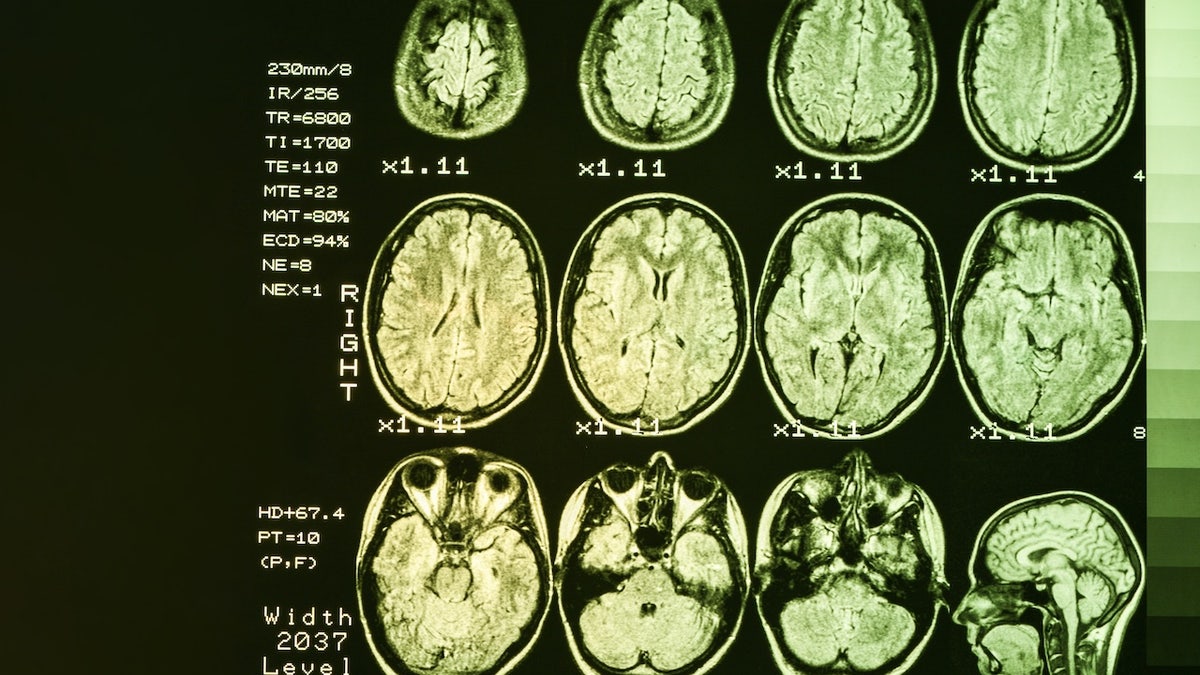

The disease, which typically emerges between 30 and 50 years of age, is caused by a mutation in the HTT gene, which triggers the cells to create a protein called huntingtin that can cause damage to the brain. (iStock)